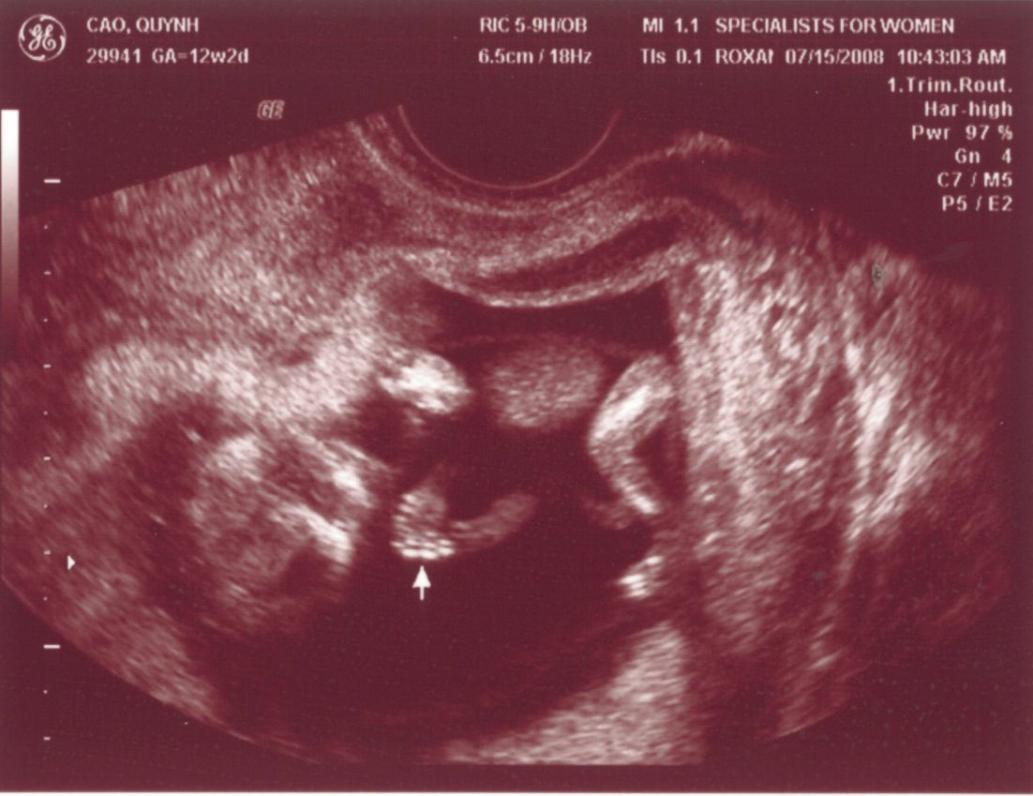

Ngày 11/28/1999 Ba Mẹ có nhau, lúc đó con ở đâu ha? Ngày 5/27/2008, con đây rồi!!! Mới được 2 tuần, là hạt nhân nhỏ xíu trong bụng Mẹ thôi Ngày 6/4/08, lần đầu tiên Ba Mẹ nghe tim con đập, 124 nhịp/phút. Mẹ sung sướng nhìn con. Còn Ba thì rơm rớm nước mắt, hihi!! Ngày 7/8/2008, con được 11 tuần rồi, bắt đầu có tay chân rồi đây... 1 tuần sau tay chân con đã dài ra rồi, lẹ ghê... ...biết nhào lộn vòng vòng nữa, mới nằm úp giờ nằm ngửa rồi. Ngày 9/3/2008, Mẹ chưa muốn biết con là trai hay gái vì muốn bất ngờ, nhưng rồi cuối cùng cũng không đợi được... ...hihi, cục cưng của Ba Mẹ là con trai. Con trai miệng bự giống Ba.  19 tuần là mắt mũi miệng đầy đủ hén. Từ khi biết có con, Mẹ nhờ Ba chụp hình hai mẹ con mình. Cái này là lúc con được 2 tháng trong bụng Mẹ.. ...24 tuần, con bắt đầu cựa quậy lung tung mỗi ngày... ...36 tuần, có lúc Ba Mẹ tưởng đã mất con nhưng con vẫn lớn giỏi ngoan... ..39 tuần, con nặng quá rồi nhưng Mẹ vẫn muốn con ở trong đó thêm chút nữa cho lớn lớn... Ba thì nôn gặp con quá, ngày nào Ba cũng nói chuyện với con.  Bụng Ba cũng bự rồi nè! Ngày 1/20/2009, con 39 tuần, bác sĩ muốn con ra sớm cho an toàn.  Ba Mẹ hồi hộp đợi tới lúc gặp con... Sau gần 8 tiếng chờ đợi thì con ra đời!! Con mở mắt nhìn Mẹ như là biết rồi đó.  Thương con ghê nơi! 1 tuần tuổi thì rụng rún.  2 tuần tuổi thì chụp hình lần đầu với Mẹ, nhỏ xíu xiu xiu... 7 tháng (8/2009) con bò lung tung, chụp hình mà không yên... 14 tháng (4/2010) con chỉ muốn chạy chơi thôi, Ba chụp lẹ lẹ nghe. Ngày 2/19/2010 Ba Mẹ làm lễ cưới ở nhà thờ.  Lần này thì có con rồi.  Có con Ba Mẹ có tất cả...